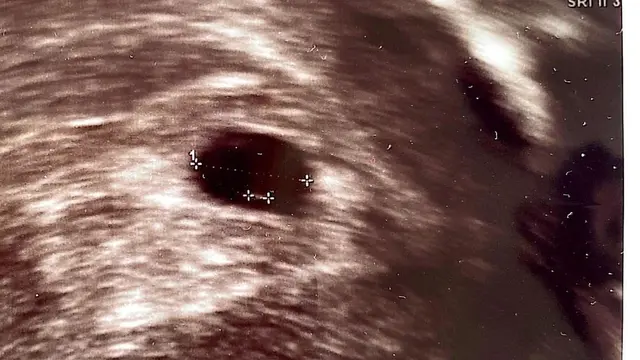

Melaui beberapa potret, Annisa bersama AHY dan putrinya. Perempuan kelahiran Bostom 40 tahun silam itu duduk di kursi roda. Sedangkan di belakangnya ada putri tunggalnya dan sang suami. Sedangkan foto lain, ada juga hasil USG perutnya.

Annisa Pohan hamil anak kedua, namun sayang pada saat usia kehamilannya tujuh minggu, janin tidak berkembang dan terpaksa harus dibersihkan.

Selain janin yang tidak berkembang, janin dalam perutnya juga tidak ada detak jantungnya.